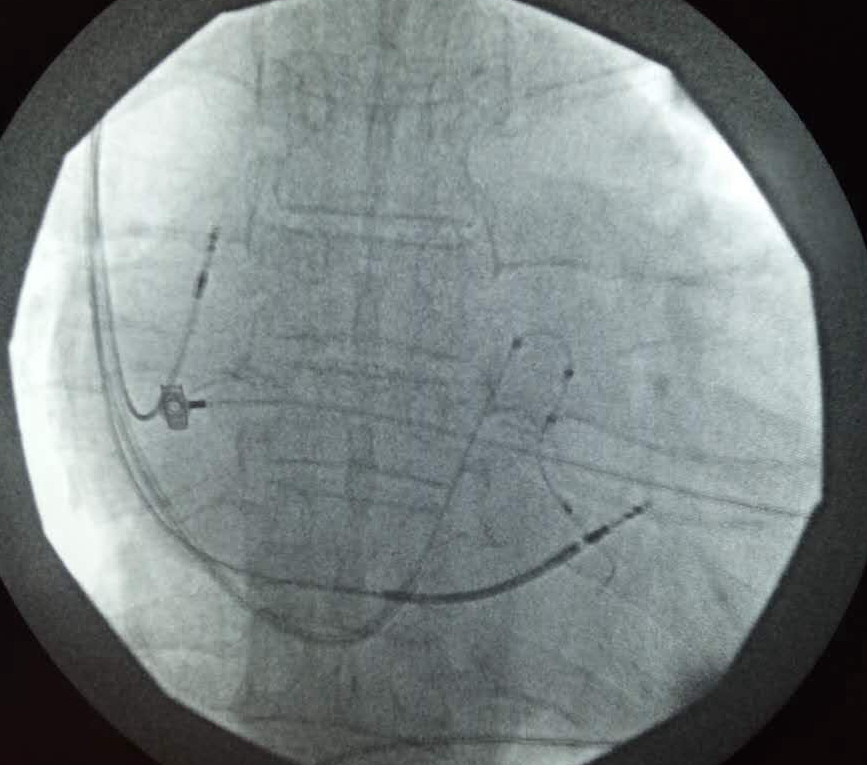

4月12日,受陇南市第一人民医院心内科二病区主任蔡文平的邀请,我省著名心内科专家、兰大一院心脏中心主任白明教授来陇南市第一人民医院指导开展CRT-D(带除颤功能的三腔起搏器)植入术,在陇南市第一人民医院放射科、泌尿外科及耳鼻喉科同仁的大力协作下,白明教授和蔡文平主任共同为一位左心及右房扩大、LVEF(左室射血分数)仅为29%、QRS时间170ms、二尖瓣反流(中-大量)并伴房颤、反复心源性晕厥的危重心衰患者成功植入CRT-D(带除颤功能的三腔起搏器),完成我市首例心脏再同步化起搏-电复律除颤器植入术。

白明教授和蔡文平主任进行CRT-D植入术

CRT-D植入成功